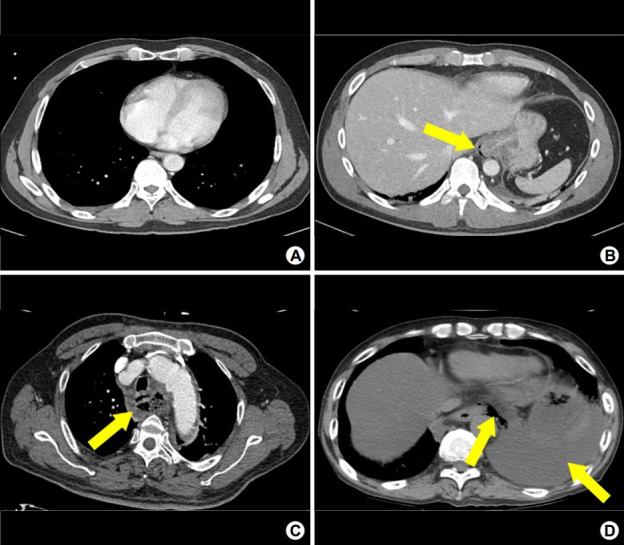

Methods: Patients admitted through the ED for evaluation of esophageal injuries between January 2001 and May 2020, were investigated. Demographic data, etiological factors, comorbidities, treatment administered, and outcomes were collected. Esophageal injury was graded based on the following CT criteria: (a) normal, (b) pneumomediastinum, (c) mediastinitis, fluid collection, abscess, or overt esophageal wall injury, and (d) pleural effusion, subcutaneous emphysema, or pneumothorax. Grade 2 was defined as microperforation and grades 3 and 4 as overt perforation.

Results: Of 281 patients with esophageal injury, 38 had CT-documented overt perforations and 20 had microperforations. Foreign body-induced injury (n=37), Boerhaave syndrome (n=12), and chemical injury (n=3) were common causes of esophageal injury. Complications occurred in 24 (8.5%) patients. Risk factors for complications were age ≥65 years (OR 4.14, 95% CI 1.18~14.56, P=0.027), cerebrovascular disease (OR 8.58, 95% CI 1.13~65.19, P=0.038), Boerhaave syndrome (OR 12.52, 95% CI 2.07~75.68, P=0.006), chemical injury (OR 15.72, 95% CI 3.67~67.28, P<0.001), and CT-documented grade 4 perforation (OR 15.75, 95% CI 4.39~56.55, P<0.001).